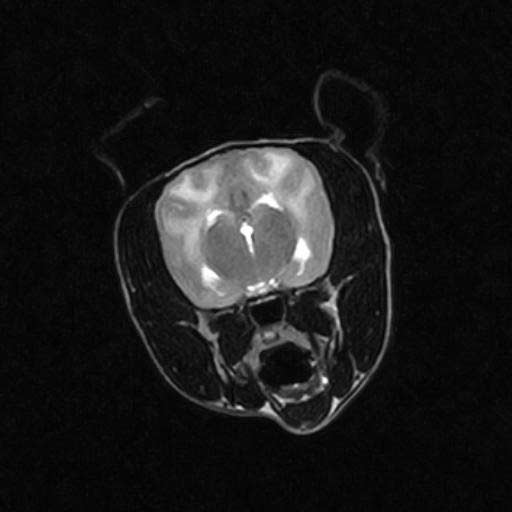

A patient’s signs cannot be used alone to diagnose MUO. Similar signs can also be caused by other neurological conditions such as cancer of the brain or bleeding into the brain. Even the most severe form of meningitis or encephalitis may not be detected by blood tests. You will always need to conduct additional tests and may recommend special imaging studies such as MRI scans in order to diagnose the problem. When done safely, cerebrospinal fluid analysis (collection of fluid around the brain) is one of the most useful tests. By doing so, it can be determined whether inflammation is present, what type of inflammation it is, and, perhaps more importantly, whether or not there is an infection present. It is rare for cerebrospinal fluid to be normal if an animal has MUO.